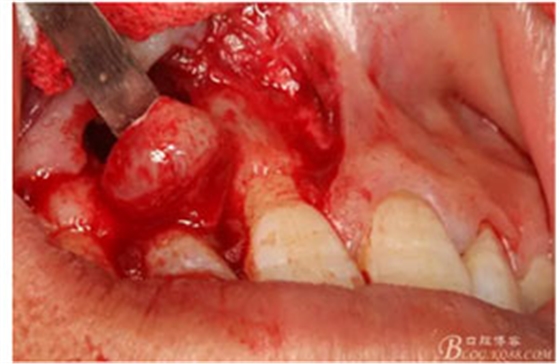

圖10。用骨膜剝離器沿著骨壁、緩慢逐漸剝離囊壁。

圖11。21囊壁被完整的剝離開來。